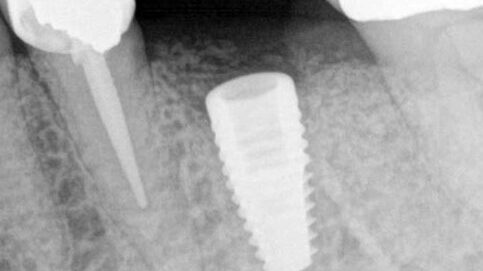

Latrogenic Inclusion of Impression Material Resulting in an Early Abutment Screw Fracture. The patient presented for retrieval of a fractured abutment screw from a Straumann 4.8 BL implant in the #19 site.